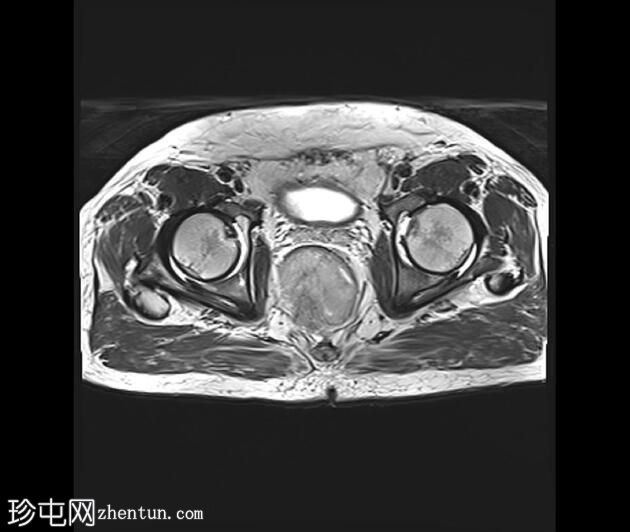

轴位

8.jpeg

T1加权像

可见一不规则分叶状肿块,累及直肠中段和远端,头尾方向长约7 cm,下缘距肛缘约2.5 cm。在T1加权像和T2加权像上,该病灶相对于骨骼肌均呈高信号。 PDFS(脂肪抑制)图像显示持续高信号强度,提示存在黑色素和/或出血成分。

增强扫描显示病灶内呈不均匀强化。直肠下段7点钟位置的系膜筋膜受累。后方系膜可见少量淋巴结。未见邻近器官侵犯。